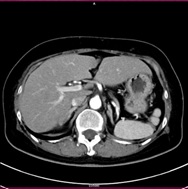

CT検査には、そのまま検査台に寝ていただき撮影する単純CTと造影剤を用いた造影CT検査があります。基本的には単純CT検査を行った後、より詳細に観察したい場合や血管などを観察する場合に行います。造影CT検査は肘(ひじ)のあたりに針を刺し血管内(静脈)に造影剤を入れて撮影します。

単純CT画像 造影CT画像 MPR画像